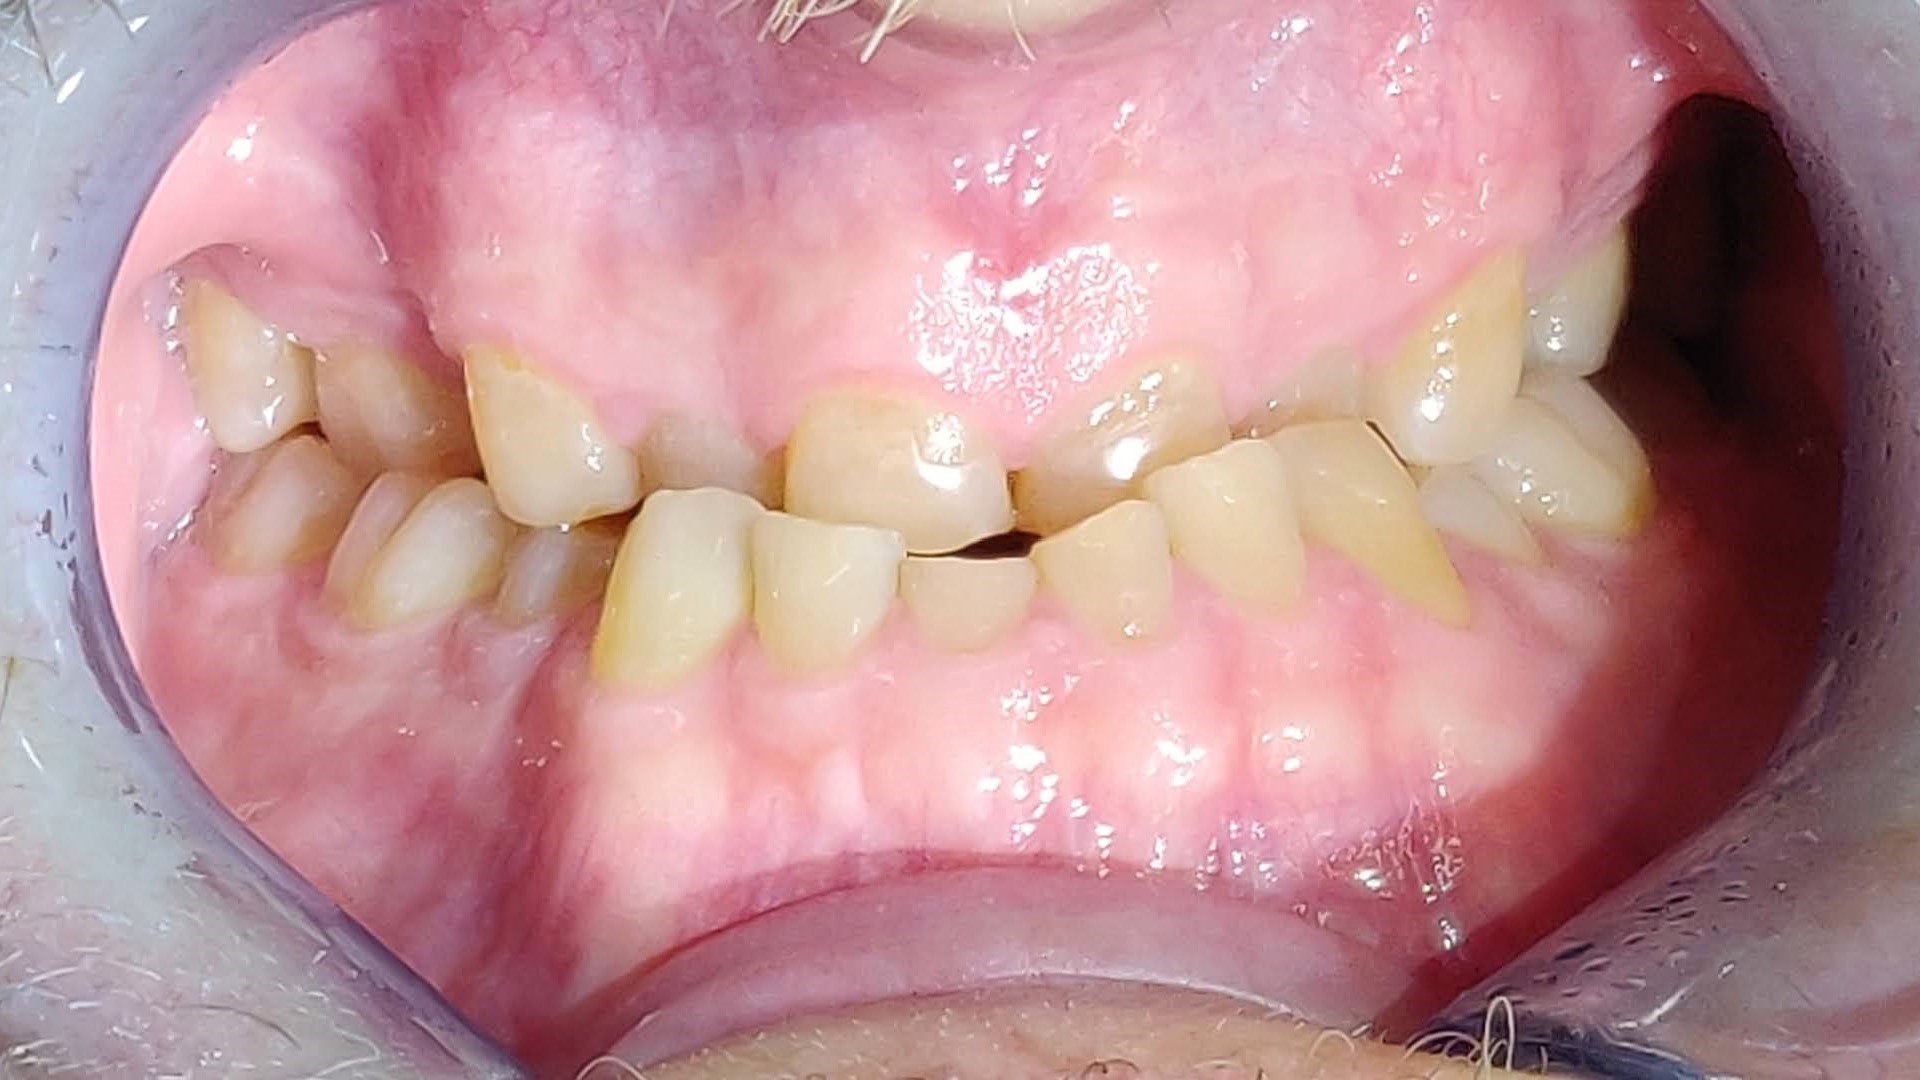

HOIDOT PURENTAVAIVOIHIN

On paljon hammasvaivoja, joihin on olemassa helppojakin hoitoja. Asiantuntevalta hammaslääkäriltä saat hammastarkastuksessa analyysin oman suusi terveydestä. Tässä kuvassa potilaan vaivana oli purressa lohkeavat hampaat. Kyseessä oli kuluneiden hampaiden väärään asentoon ohjaama (eli ristipurentaan) purenta ja sen myötä syntyneet lisävauriot, kulumat ja lohkeamat. Nämäkin hampaat hoidettiin kuntoon, suun terveys palautui ja ilmeestä tuli entistä ehompi, raikas ja hurmaava. Lue koko purentahoidon eteneminen tästä ja katso hämmästyttävät kuvat ennen ja jälkeen.

purentavirhe, ristipurenta